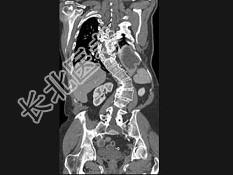

- 单项选择题男,24岁, 四肢细长,蜘蛛指, 肌张力降低,结合图像, 最可能的诊断是 ( )

C、马方综合征